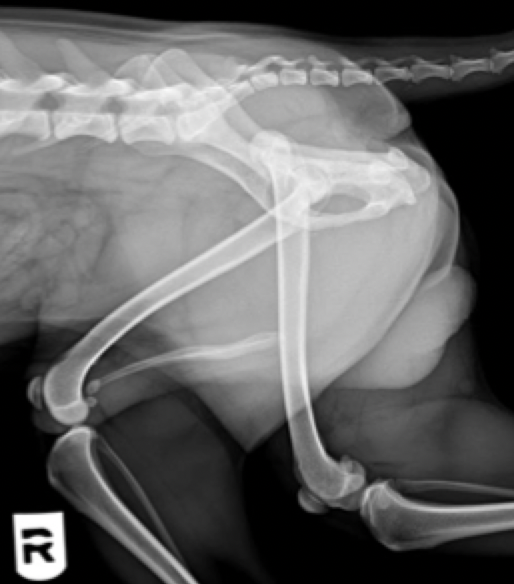

Flattening of the caudal humeral head (most common site)

due to Osteochrondritis Dissecans (OCD)

looks flatter bc cartilage is becoming thicker and thicker

will often be bilateral

large, fast growing dogs are predisposed